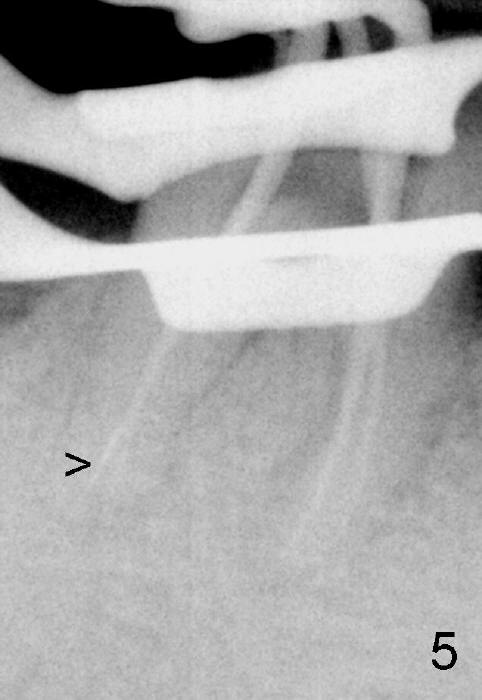

五十来岁郑先生缺失两个下颌第二磨牙,严重牙齿磨耗,三年前主诉右下第一磨牙冷热痛(可能与磨耗有关),近中有轻度根尖阴影(图一箭头),初步CT检查表明该牙齿有四个根管(图二,三),兴高采烈,这样不会错过远中舌侧根管(DL),开髓发现根管几乎阻塞,尤其是远中舌侧,hand files不容易进入根尖,使用20/.04 rotary file时,在根尖断裂(图四箭头,其余根管插入30/.06牙胶尖),一时不能bypass断针,暂封。十二天后,重新bypass断针,终于成功,但是取不出断针,扩大二十号hand file(远中舌侧根管),图五,图六侧方充填(lateral condensation)之前,图七之后(图六,七*:近中阴影)。根管治疗和牙冠之后一直无症状,一年半在第二磨牙处植牙(图八I),虽然第一磨牙近中根尖阴影增大(*),但离植牙还有一定距离,可能不会产生问题。不过不久植牙松动,病人自己取出,可能当时钻洞太大,而不够深(no primary stability),怕侵犯下颌神经(图八红线)。十个月后再次试图植牙(图九D:钻头),突然发现智齿(阻生)在手术视野之中,而且智齿咬合面不干净,结果取消植牙,把智齿拔除,这时病人第一磨牙仍没有症状,但是根尖阴影不可观(图九*),远中舌侧根尖好像没有病变(箭头)。大概这次智齿拔除也与左下智齿七拔除(左下第二磨牙植牙之前)一样不舒服,郑先生一直没有回来做右下第二磨牙植牙。上周六他终于登门,右下第一磨牙出现根尖脓肿症状(术后近三年),根尖片如图十。S代表已经愈合智齿牙槽窝,根尖阴影不小,断针根尖仍没有阴影。